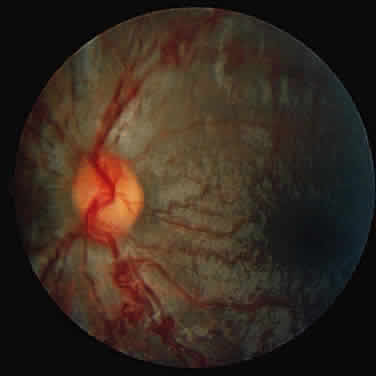

Corneal clouding (Fig. 10), hyperopic astigmatism, and a mild retinopathy with surface-wrinkling maculopathy (Fig. 11) appear to be the constant ocular triad.75 Some patients have retinal vascular tortuosity, optic nerve head swelling (Fig. 12), visual field defects, and abnormalities in color vision. Visual complaints are uncommon.

Fig. 11. Surface-wrinkling maculopathy in a patient with mucolipidosis III. (Traboulsi E, Maumenee I: Ophthalmologic findings in mucolipidosis III. Am J Ophthalmol 102:529, 1986)

Fig. 12. Optic nerve head swelling in a patient with mucolipidosis III. (Traboulsi E, Maumenee I: Ophthalmologic findings in mucolipidosis III. Am J Ophthalmol 102:529, 1986)